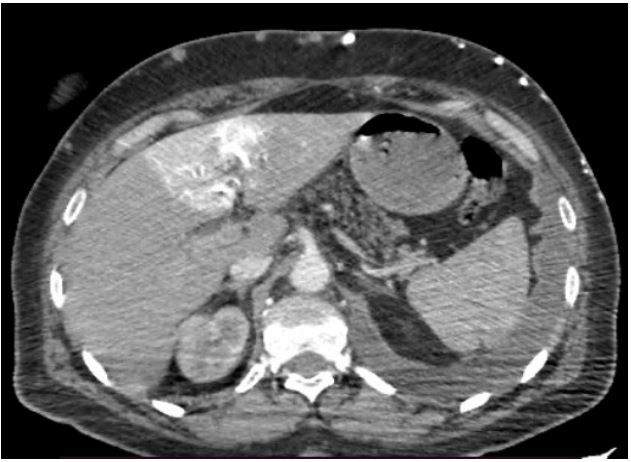

A 51‐year‐old women was hospitalized to start chemotherapy for small cell lung cancer diagnosed one months earlier. She underwent Computed Tomography (CT) of the chest and abdomen to re‐evaluate the progression of the lung tumour. Contrast-enhanced CT of the chest indicated an invasive anterior left lung tumour that caused an obstruction of the Superior Vena Cava (SVC) (Figure 1). Contrast-enhanced CT of the abdomen revealed an intense focal wedge-shaped homogeneous enhancement area in the quadrate lobe of the liver, which is known as the hot spot sign (Figure 2). Focal hepatic hot spot sign was first described by Ishikawa in 1983. The sign can be observed on technetium 99m (99mTc) Sulphur colloid scans or on contrast, material enhanced CT scans [1]. Hot spot sign is caused by portosystemic venous shunting between the superior vena cava and the left portal vein via the internal mammary and paraumbilical veins along the ligamentum teres, secondary to superior vena cava obstruction. The hot spot is created by areas of focally increased blood flow that result from this shunting [2]. Stanford and colleagues classified SVC syndrome into four types - type I and type II referred as supra-azygous partial and near complete obstruction of SVC with antegrade flow in azygous vein. Type III is defined as complete obstruction of SVC with reversal of azygous blood flow and type IV as complete obstruction of SVC and azygous system with development of chest wall collaterals [3]. This sign has been reported in Budd-Chiari syndrome, the causes of SVC syndrome (neoplasms of the thorax as lung carcinoma and lymphoma, Vasculo‐Behcet’s disease, fibrosing mediastinitis, and luetic aneurysm), and masses of the liver (abscess, haemangioma, focal nodular hyperplasia, and hepatocellular carcinoma) [4].

Figure 2: